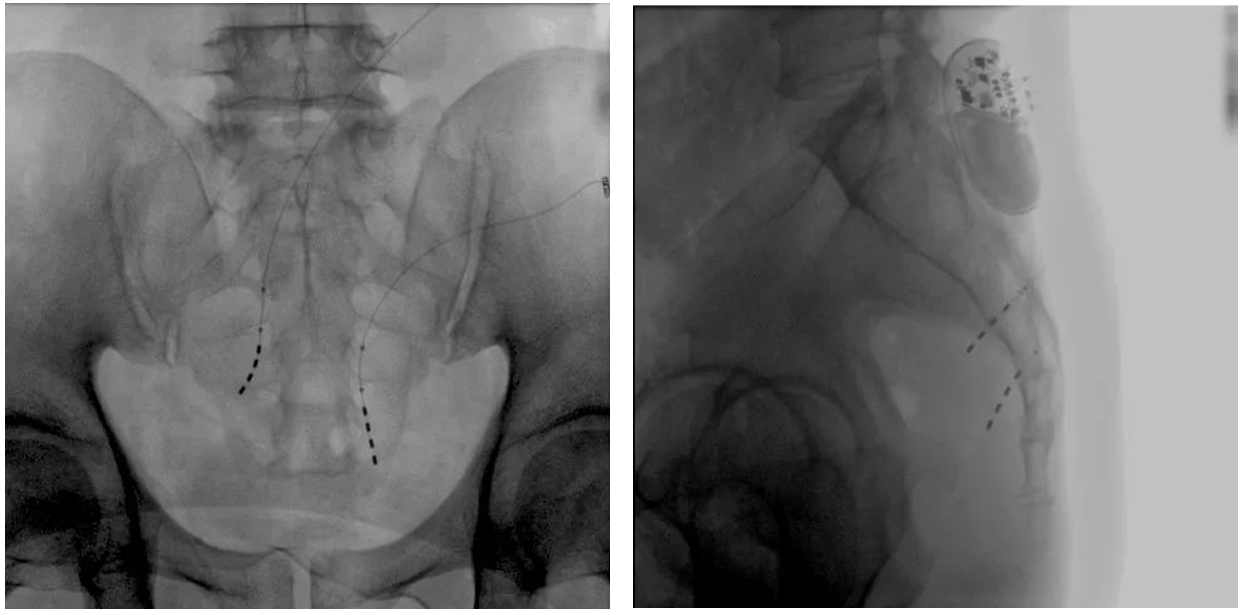

大平板一體式移動C形臂術(shù)中影像

在骶神經(jīng)調(diào)控術(shù)或者骶神經(jīng)刺激術(shù)(SNS)中,醫(yī)師首先會在透視引導(dǎo)下把電極通過導(dǎo)針插入到骶3神經(jīng)孔位置,通過脈沖電流的刺激,達(dá)到興奮神經(jīng)纖維并抑制逼尿肌收縮。在這一步,醫(yī)師會先對患者的神經(jīng)刺激反應(yīng)做測試評估,如果刺激效果明顯,說明該方案能夠達(dá)到手術(shù)預(yù)期。接下來醫(yī)師會在附近皮下脂肪處植入一塊脈沖電流發(fā)生器并與電極相連,使該部位今后能得到長期的電刺激,改善OAB癥狀。

? 傳統(tǒng)9英寸的平板探測器或影像增強器C形臂,成像范圍較小,在進行導(dǎo)絲定位觀察時,受手術(shù)床的限制無法呈現(xiàn)大視野的透視圖像,需要進行多次的拍攝,降低手術(shù)的效率。而普愛醫(yī)療大平板一體式移動C形臂裝備一塊30cm x 30cm大平板探測器,超大的成像區(qū)域彌補了因擺位不便造成的拍攝困難。

? 相較于影增C形臂,平板探測器成像的畸變更少,能夠準(zhǔn)確體現(xiàn)電極和骶孔位置關(guān)系,提高手術(shù)效果預(yù)期。